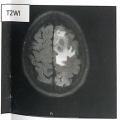

| Imaging:(Click to enlarge) | 患者胸部 CT检查:胸廓两侧基本对称,两肺纹理增多,气管及各叶、段支气管管腔通畅。支气管壁增厚。左肺见囊状薄壁透亮影。两肺散在斑片状密度增高影。两侧肺门结构清楚,两侧肺门旁及纵隔内未见明显肿大淋巴结。纵隔居中,心包未见增厚及积液;心脏饱满,主动脉及冠状动脉壁见斑点状致密影。两侧胸膜未见异常,两侧胸腔见窄弧形积液。 检查结论:两肺散在炎症;左肺肺大泡。 患者 MRI检查:左额叶见多发结节状异常信号影,大者位于颅板下,大小约2.6cmx1.6cmX2.8cm,T1WI呈低等信号,T2W!呈不均匀稍高信号,边缘 DWI 呈高信号,ADC 呈低信号,边界欠清楚,增强后病灶明显环形不均匀强化,周围见环形T1WI低、T2WI高信号水肿带。 检查结论:左额叶多发占位(较前2025-08-09片范围增大),考虑恶性肿瘤,转移瘤待排,请结合临床,建议进一步PET-CT检查。